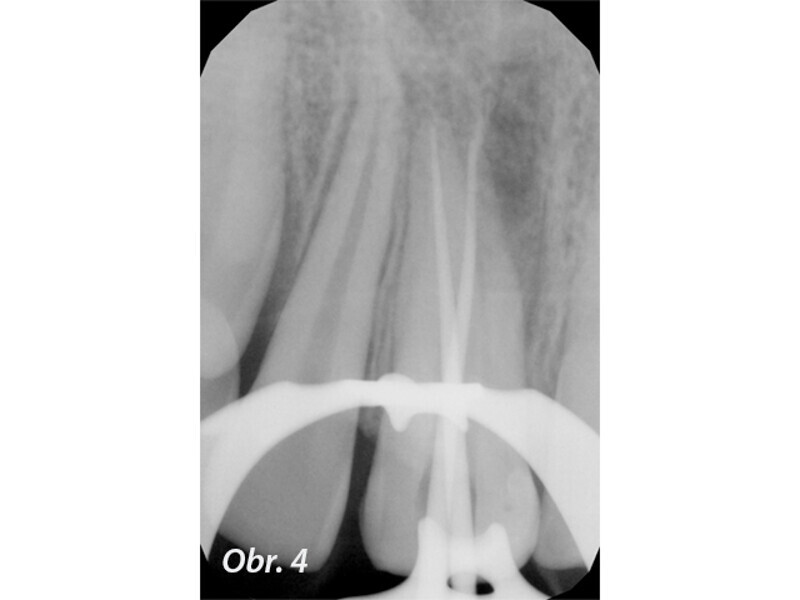

Endodontické ošetření horního středního řezáku s atypickou anatomií